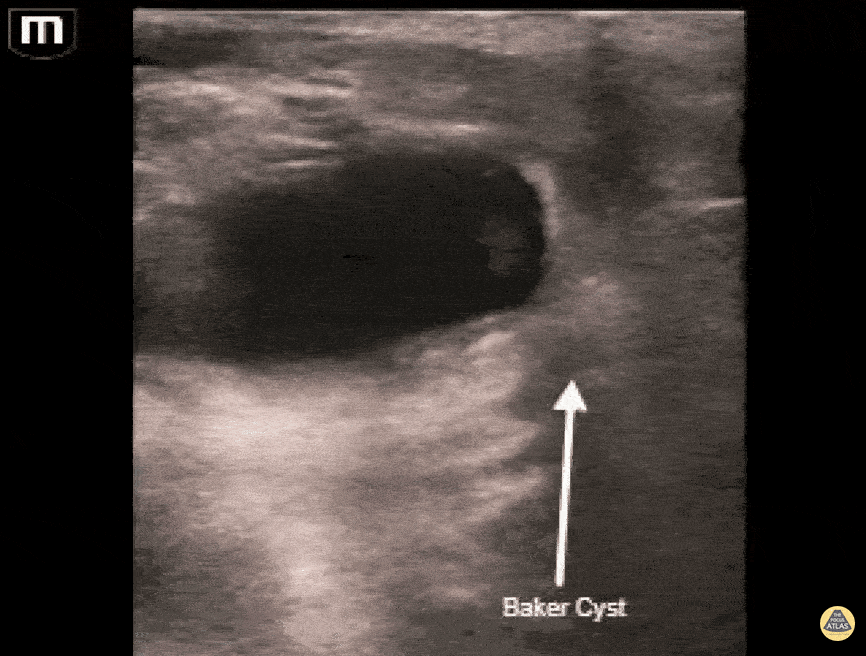

Musculoskeletal - Baker's cyst causing leg pain

Patient in their 50s presented for leg pain that has gradually worsened over the past few days. Bedside lower extremity ultrasound was completed to evaluate for blood clot. It demonstrated a Baker's cyst, the hypo echoic area above the popliteal vasculature. Mehtab Galeh, MD Emergency Medicine Resident PGY3 Central Michigan University; Bayley Espinoza, MD Emergency Medicine Resident PGY1 Central Michigan University